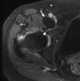

Synovial hypertrophy secondary to arthritis